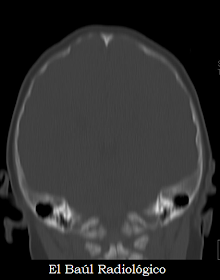

Normalmente no se suelen detectar, salvo que por otro motivo: sospecha de craniosinostosis o un traumatismo craneoencefálico, haya que realizar una exploración de Tomografía Craneoencefálica a un neonato. El aspecto del cráneo, que parece lleno de grandes agujeros, (Figura 1b) resulta sorprendente.

FIGURA 1b) Craneolacunia. Imagen de TC. Reconstrucción Sombreada de Superficie (SSD Siemens). Visión coronal de la calota craneal con las típicas lagunas que afectan a los huesos parietales y occipitales.

En proyección coronal también se observan las lagunas craneales que se localizan en la convexidad de los huesos parietales y occipitales.